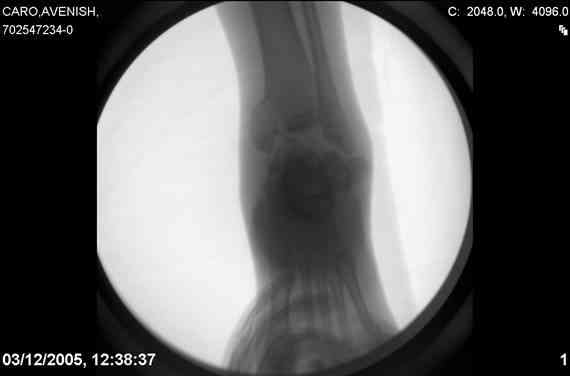

Re: Осколчатый перелом таранной кости

ya by popytalsya sobrat talus anatomichno,seichas pozdno operirovat iz za oteka,po etomy distrakziya apparatom budet optmalna.Posyalu vam podobyai moi sluchai.

14 years old girl

Fall from height ( 3rd floor)